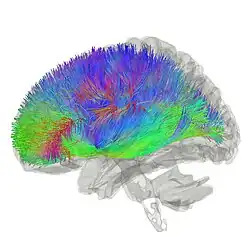

![]() Tractography showing corticostriatal connections | |

Inputs

The largest connection is from the cortex, in terms of cell axons. Many parts of the neocortex innervate the dorsal striatum. The cortical pyramidal neurons projecting to the striatum are located in layers II-VI, with the most dense projections come from layer V.[35] They end mainly on the dendritic spines of the spiny neurons. They are glutamatergic, exciting striatal neurons.

The striatum is seen as having its own internal microcircuitry.[36] The ventral striatum receives direct input from multiple regions in the cerebral cortex and limbic structures such as the amygdala, thalamus, and hippocampus, as well as the entorhinal cortex and the inferior temporal gyrus.[37] Its primary input is to the basal ganglia system. Additionally, the mesolimbic pathway projects from the ventral tegmental area to the nucleus accumbens of the ventral striatum.[38]

Another well-known afferent is the nigrostriatal connection arising from the neurons of the substantia nigra pars compacta. While cortical axons synapse mainly on spine heads of spiny neurons, nigral axons synapse mainly on spine shafts. In primates, the thalamostriatal afferent comes from the central median-parafascicular complex of the thalamus (see primate basal ganglia system). This afferent is glutamatergic. The participation of truly intralaminar neurons is much more limited. The striatum also receives afferents from other elements of the basal ganglia such as the subthalamic nucleus (glutamatergic) or the external globus pallidus (GABAergic).